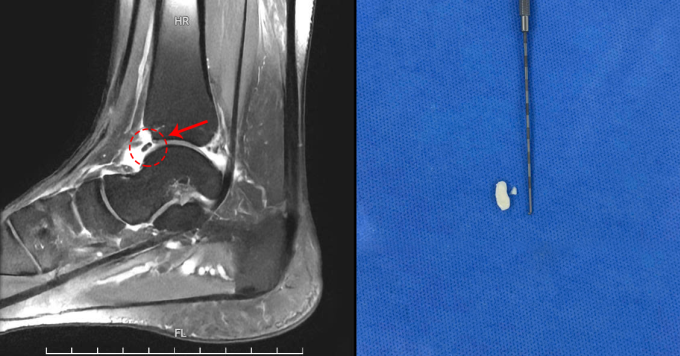

BS.CKII Trần Tuấn Anh, Khoa Chấn thương Chỉnh hình, Bệnh viện Đa khoa Tâm Anh Hà Nội, cho biết kết quả siêu âm, chụp X-quang và cộng hưởng từ MRI, ghi nhận mảnh xương di động kích thước 3,6x1,6 mm gây hội chứng chèn ép khớp cổ chân kèm viêm bao hoạt dịch khớp cổ chân.

Bác sĩ cho rằng đây là mảnh sụn khớp bong ra khi chị Hương ngã xe một năm trước, lâu dần vôi hóa. Khi chị vận động, đôi lúc mảnh xương hoặc sụn lọt vào giữa khe khớp hoặc dây chằng, mắc kẹt gây đau chói. Qua thời gian, mảnh dị vật trôi khỏi vị trí kẹt nên chị Hương tự nhiên hết đau, vận động bình thường. Quá trình này ngẫu nhiên nên các đợt đau xuất hiện và biến mất không theo quy luật, có thể đau 1-2 ngày hay cả tuần, có tháng không đau nhưng có tháng đau nhiều lần. Gần đây chị khẽ chạm chân xuống đất đã rất đau, không đi lại được.

Bác sĩ Tuấn Anh phẫu thuật nội soi cho chị Hương để lấy mảnh xương và sụn ra ngoài. Bác sĩ ứng dụng phẫu thuật nội soi khớp cổ chân với hai đường mổ nhỏ 0,5 cm phía trước trong và trước ngoài khớp cổ chân để đưa trocar, camera vào khớp, đánh giá các tổn thương. Bác sĩ cắt lọc bao hoạt dịch viêm, lấy mảnh xương và sụn ra ngoài, kiểm tra không còn dị vật trong khớp sau đó đóng vết mổ và băng ép.